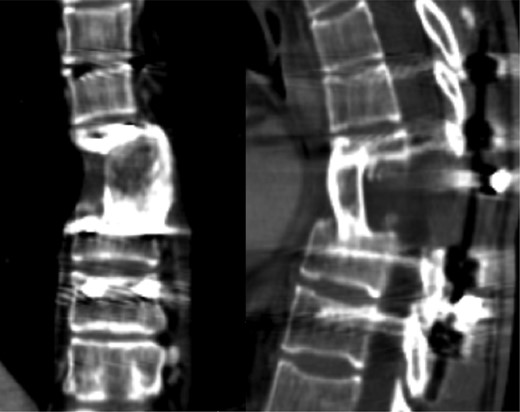

The patient started the pulmonary rehabilitation protocol by the second postoperative day, showing encouraging progression. However, by the third day, she initiated complaints of progressive dyspnea with associated impaired gas exchange. A CT scan confirmed bilateral hemothorax requiring bilateral thoracentesis (Fig. 4), after which she immediately recovered from the previous symptoms.

It was only by the 19th postoperative day, which the patient showed worsening of her general status with fever, dyspnea, decreased gas exchange and an increase in inflammatory markers. A new CT scan was performed, revealing a moderate fluid collection in both lungs, compatible with empyema (Fig. 5). The patient evolved to a septic state, which required her to be transferred to the intensive care unit.